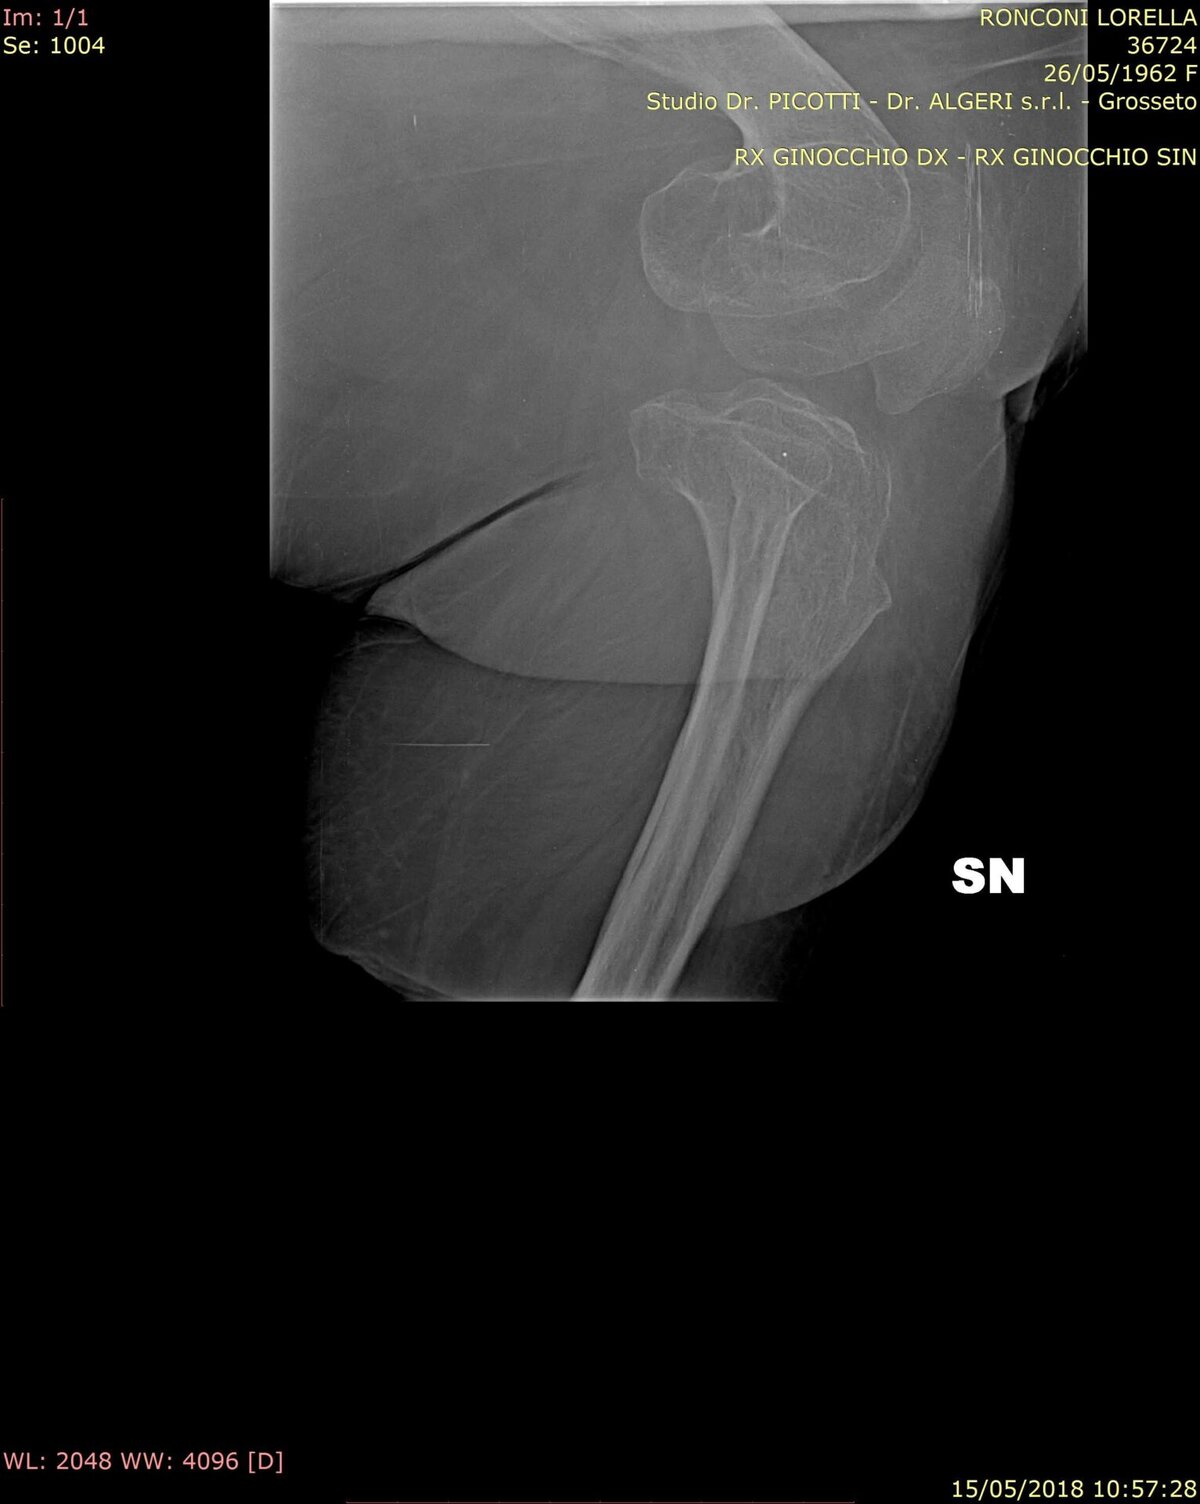

La diagnosi di pseudoacondroplasia si basa sull’insieme di segni clinici, reperti radiologici caratteristici e su un’accurata anamnesi del paziente. In particolare, gli esami radiografici evidenziano anomalie dei centri di accrescimento delle ossa (epifisi) e altre alterazioni scheletriche tipiche della patologia.

Tecniche di imaging più avanzate, come la risonanza magnetica (RM) e la tomografia computerizzata (TC), possono essere utilizzate nel corso della vita per valutare lo stato dello scheletro, in particolare in preparazione a interventi chirurgici finalizzati alla correzione delle deformità.

Esempio di sezione “La mia esperienza personale”

La mia condizione è unica al mondo, dovuta a una mutazione genetica rara e non presente in altri membri della mia famiglia. Questa mutazione, identificata come c.1576G>T (p.Val526Phe) nel gene COMP, altera la proteina fondamentale per la formazione e il mantenimento della cartilagine. Il mio decorso clinico è stato particolarmente complesso: l’osteoporosi e la fragilità articolare hanno provocato fratture e deformità già in giovane età, incluso un incidente al femore a 14 anni e la rottura a 22. Nel 1991 ho subito un intervento chirurgico sperimentale per la grave scoliosi, che stava compromettendo i polmoni e il midollo spinale.